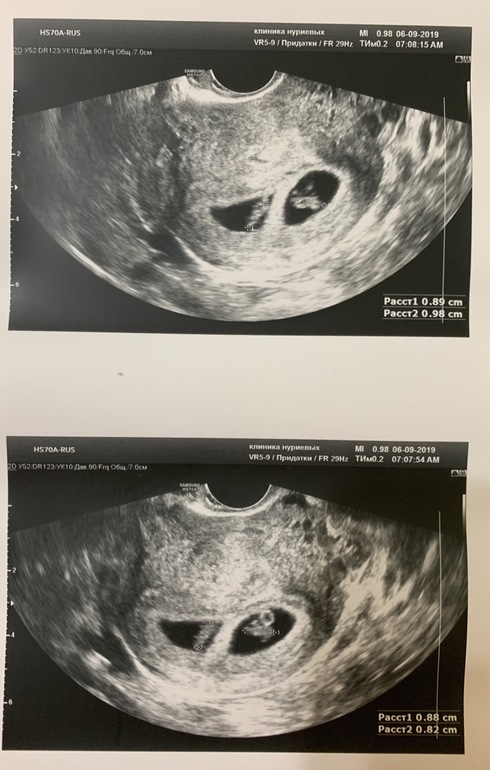

Я БЕРЕМЕННА !Вчера ходила на узи и мою двойняшковую беременность подтвердили)))

1: КТР 9 мм, сердцебиение ритмичное

2: КТР 9 мм, сердцебиение ритмичное

Срок 7 недель 2 дня)))